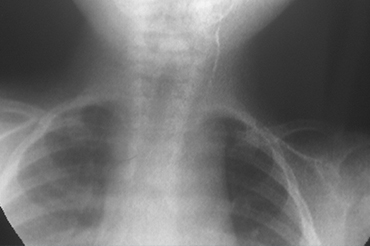

Fistula Branquial